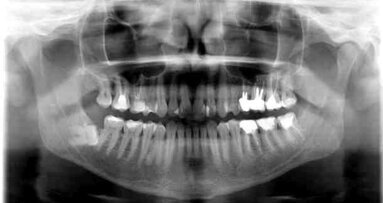

W diagnostyce otwartego DNP stosuje się wprowadzanie ćwieków gutaperkowych z wykonanym następnie zdjęciem rtg. Dzięki stosunkowo miękkim i elastycznym ćwiekom gutaperkowym wymienione kanały (otwory DNP znajdują się z reguły w bocznej lub tylnej konfiguracji do brodawki przysiecznej) mogły zostać uwidocznione, nie sprawiając bólu pacjentom.

Do obrazowania PNPD wypełnianych za pomocą ćwieków gutaperkowych nadaje się w szczególny sposób technika obrazowania 2D i 3D (tomografia komputerowa, CBCT, MRI) (Knecht i wsp. 2005, Catros i wsp. 2008).